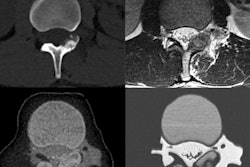

The lab will install a variety of the company's applications on its aycan workstation software from radiology informatics firm Aycan Medical Systems for imaging brain tumors and assessing treatment response. Among the applications is the company's IB Rad Tech program, which makes it easy and repeatable to generate image maps such as fractional tumor burden.